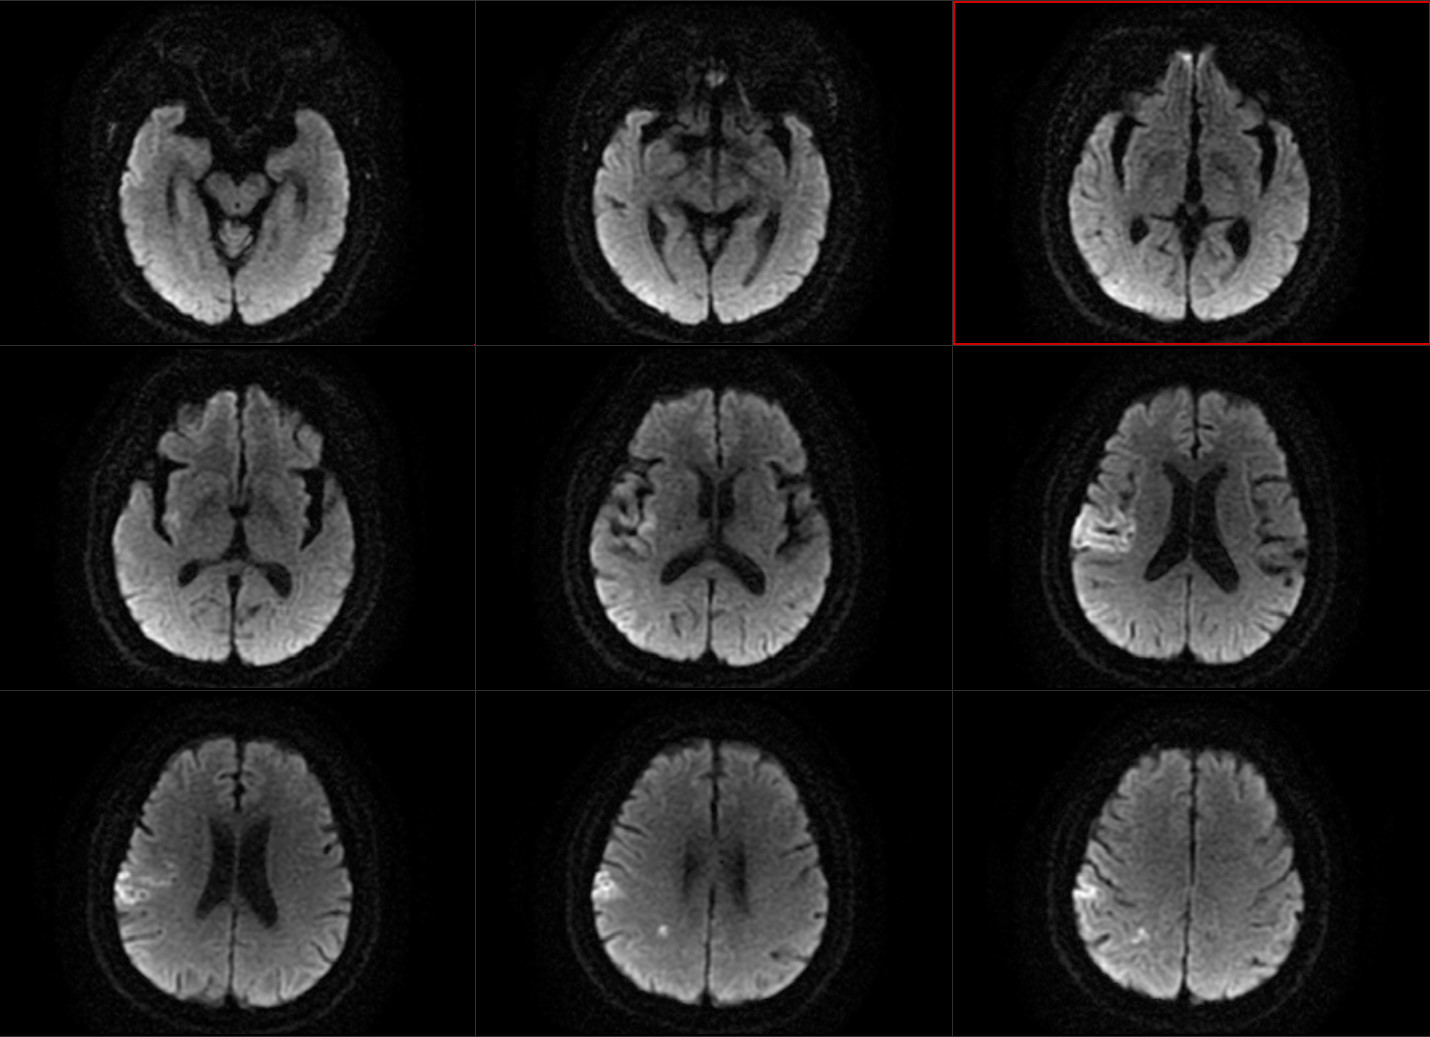

醫生可不敢怠慢,仔細讀片,發現在老林的腦裏,果然分布着兩片腦梗死:一片是這次新發,另一片是陳舊性的。值得留意的是,四次中風堵塞的還都是不同血管!